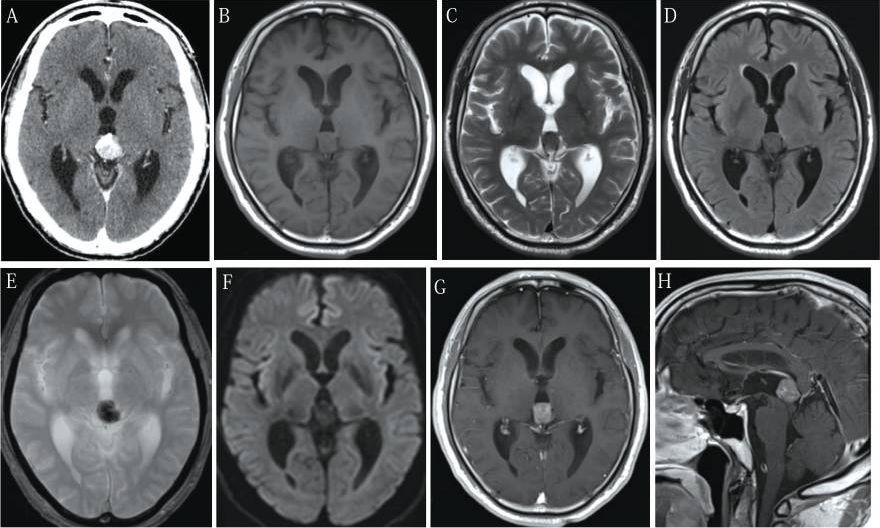

62岁男性,主诉复视病史1个月。60岁时,患者有紧张性头痛,曾行磁共振成像(MRI)检查,未见异常表现(图1)。MRI两年后,患者行计算机断层扫描(CT)和磁共振成像(MRI)检查复视。CT显示肿瘤呈增强形态,直径3cm,松果体区可见钙化(图2A)。肿瘤在t1加权MRI上呈等强度(T1WI,图2B);T2WI微低信号(图2C)和流体衰减反演恢复图像(图2D);T2* WI低信号明显(图2E),扩散WI明显(图2F), T1WI上钆异质增强(图2G)。钆增强T1WI矢状面显示垂体神经区未见肿瘤(图2H)。脑积水是由于肿瘤引起导水管狭窄所致。病人转到我们医院治疗。入院后复视好转,眼球运动充分平稳。经简易心理状态检查和韦氏成人智力量表检查,其心理功能轻度恶化。他的下面血清肿瘤标记物在正常范围:甲胎蛋白,β人体绒毛膜促性腺激素(βhcg)、癌胚抗原、β2-microglobulin,促黄体激素5.2个人/毫升(参考价值:1.7 - -11.2)、促卵泡激素9.2个人/毫升(参考价值:2.1 - -18.6),和睾酮482.0毫微克/分升(参考价值:220.9 - -715.8)。脑血管摄影显示一个微弱的肿瘤染色没有任何动静脉分流。CT检查未发现有转移到脑的肿瘤。因此,在鉴别诊断时要考虑多种肿瘤,如松果体实质肿瘤、神经胶质瘤、不明来源的转移性肿瘤和海绵状血管瘤。随后患者行内镜下活检和三脑室造口术,经右额冠状前刺孔及可操作的电视镜检查。肿瘤很容易在松果体区发现一个灰色肿块,包含旧时出血和钙化(图3A),怀疑转移到漏斗部(图3B)。活检标本取自几个不同的部位。活检时肿瘤有少量出血,冲洗可轻易止血。术后无并发症发生。术中脑脊液(CSF)β-HCG为0.12 mIU/mL,略升高。脑脊液中未检测到肿瘤细胞。组织病理学上,肿瘤呈2细胞型,上皮样细胞大,淋巴细胞小。前一个细胞经胎盘碱性磷酸酶(图4C)和c-kit(图4D)染色呈阳性。未观察到其他GCT成分。因此,此肿瘤的组织病理学诊断证实为纯生殖细胞瘤。患者接受单剂量放射治疗:脑室播散小剂量预防照射(25.2 Gy),原发肿瘤部位放射增强(25.2 Gy), MRI未见脊髓播散征象。放疗后肿瘤完全消失,无神经功能缺损。脑脊液β-HCG水平恢复正常。经过4年的放射治疗后,连续的MRI随访研究和β-HCG检测没有发现肿瘤复发。

图2:入院前立即行电脑断层扫描(CT)及磁共振成像(1.5特斯拉)。注意松果体区肿瘤在CT上显示混合密度和钙化(A);t1加权图像等强度(T1WI) (B);T2WI轻度低信号(C)和液体衰减反演恢复图像(D);T2*WI (E)低信号明显,弥散WI (F);钆增强矢状面T1WI (H)上垂体神经区未见肿瘤。